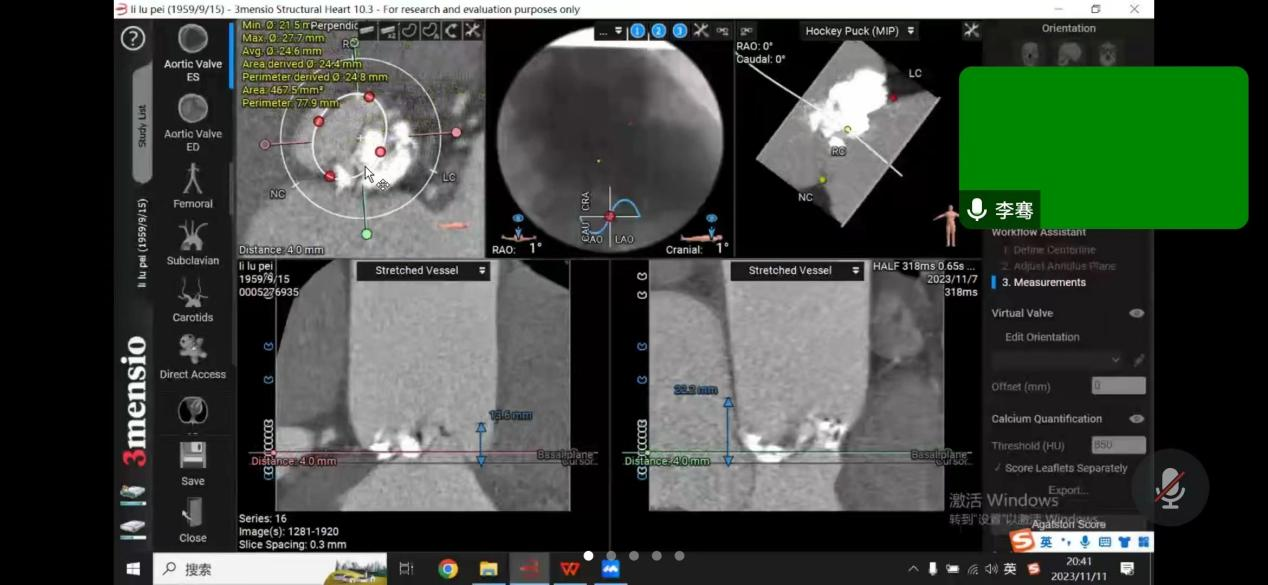

患者是一位64岁男性,反复胸闷憋气多年,未规律就诊,此次因慢性心力衰竭急性加重,心源性休克,多器官衰竭,由基层医院转至昆医大附二院。经过医院ICU团队抢救治疗后,患者病情转危为安;随后为患者完善超声心动图检查,提示主动脉瓣病变,TYPE-0型二叶式主动脉瓣,主动脉瓣钙化、重度狭窄并轻度反流,二尖瓣中度反流,三尖瓣中度反流,主动脉瓣前向血流速度4.9m/s,峰值压差95mmHg,行主动脉瓣换瓣治疗指针。由于能够反应患者左心室收缩功能的射血分数(EF值)仅占23%,心功能差,基础情况差,升主动脉瘤样扩张,收缩期心室增大明显,左室内径达60mm,心尖薄,不能承受开胸换瓣手术。心内科介入下行TAVR治疗的难度在于该病人为一例典型Type0型二叶式主动脉瓣重度狭窄患者,人工瓣膜定位及锚定难度大,患者瓣叶重度钙化,存在人工瓣膜形变、瓣环撕裂、根部损伤以及术后出现瓣周漏等风险。楚天舒主任团队对患者病情进行整体评估后,将患者情况汇报医院医务处,医务处组织心血管内科、麻醉手术科、心脏血管外科、重症医学科等进行术前多学科联合会诊,结合患者实际情况,多次讨论,为患者制定最佳手术方案,最后决定给该患者行介入导管微创瓣膜手术(TAVR)。多位专家一起制定了详尽的诊疗及手术方案,并准备了多套的应急预案。

11月12日下午,楚天舒主任团队成功为患者进行了TAVR换瓣治疗,手术中通过导管测量得到植入前心室主动脉压力差大于90mmHg,提示主动脉瓣狭窄已严重阻碍心脏正常泵血工作。人工瓣膜成功植入后,可见人工瓣膜瓣叶开阖自如,心脏对外泵血压力明显减轻,导管测得压力阶差降至10mmHg以下,血流动力学即刻得到改善。这提示着患者的主动脉瓣狭窄情况,已较前大为缓解,手术圆满成功。术后患者生命体征平稳,带气管插管安全返回ICU特护。一天后,患者被转回心血管内科二病区继续治疗。在心血管内科二病区全体医务人员的精心治疗与av线上下,患者于17日顺利出院。